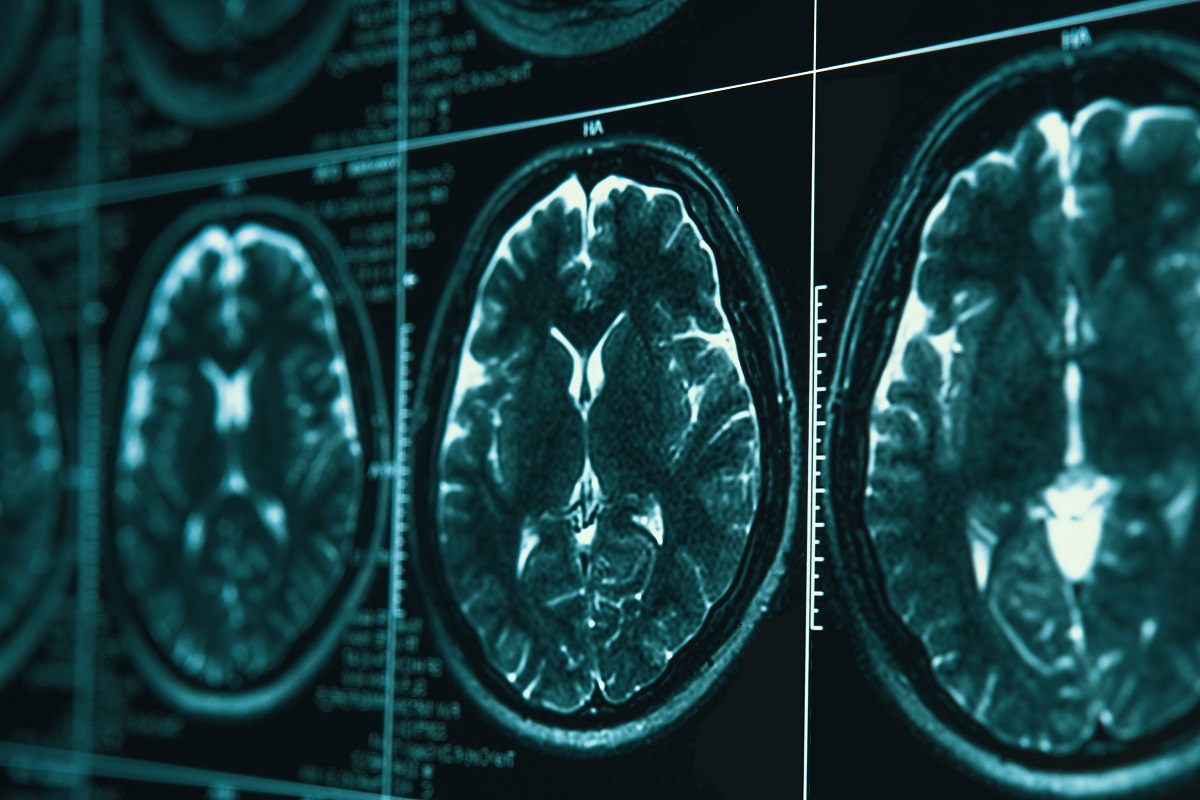

Traumatic Brain Injury

A traumatic brain injury (TBI) can have devastating consequences, affecting your physical and cognitive abilities. Whether caused by a car accident, slip and fall, or other incident, a TBI can lead to significant medical expenses, lost wages, and emotional distress.